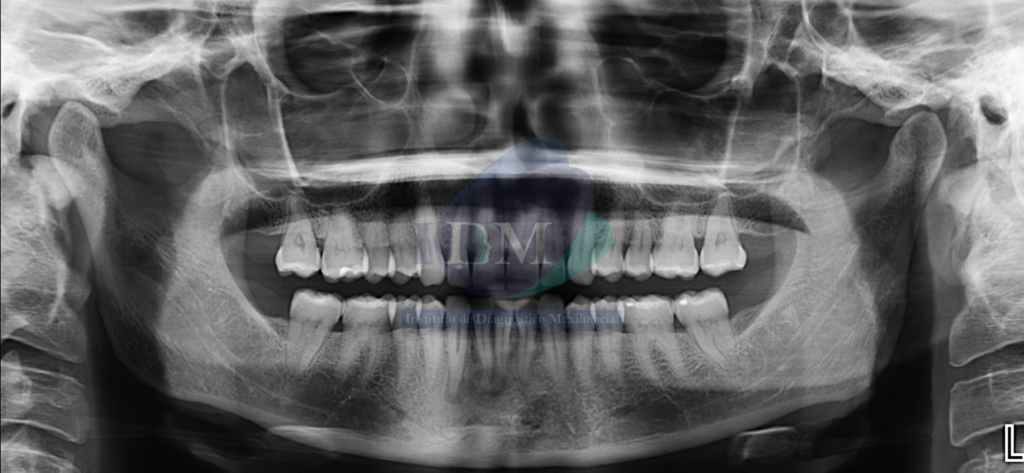

Radiografia Panorámica

A la evaluación de la radiografía panorámica se evidencian múltiples imágenes mixtas y de forma irregular en zona apical de las piezas 41, 42 y 43.